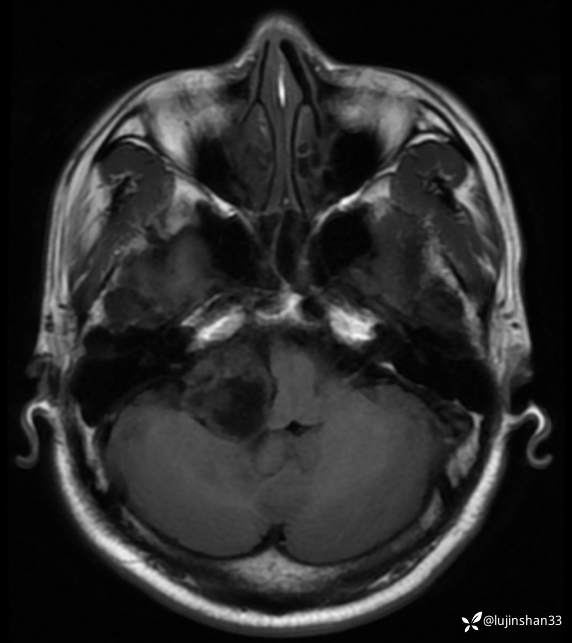

术前CT及MRI